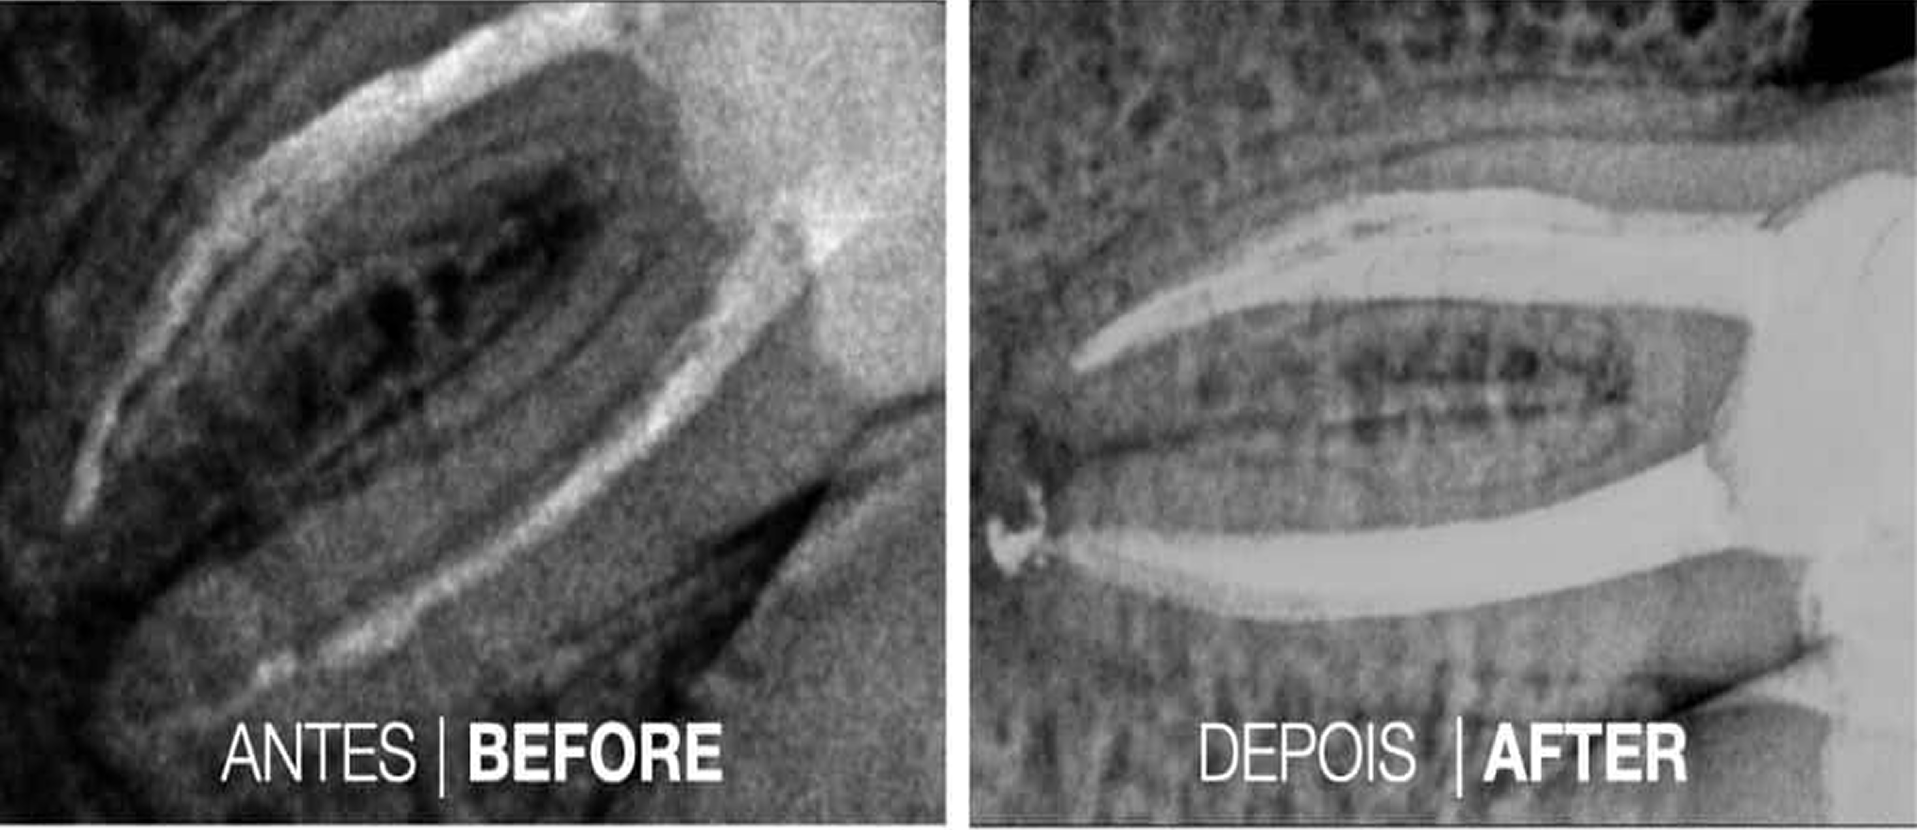

Casos Clínicos

Casos Cínicos concretos que revelam a eficácia do tratamento.